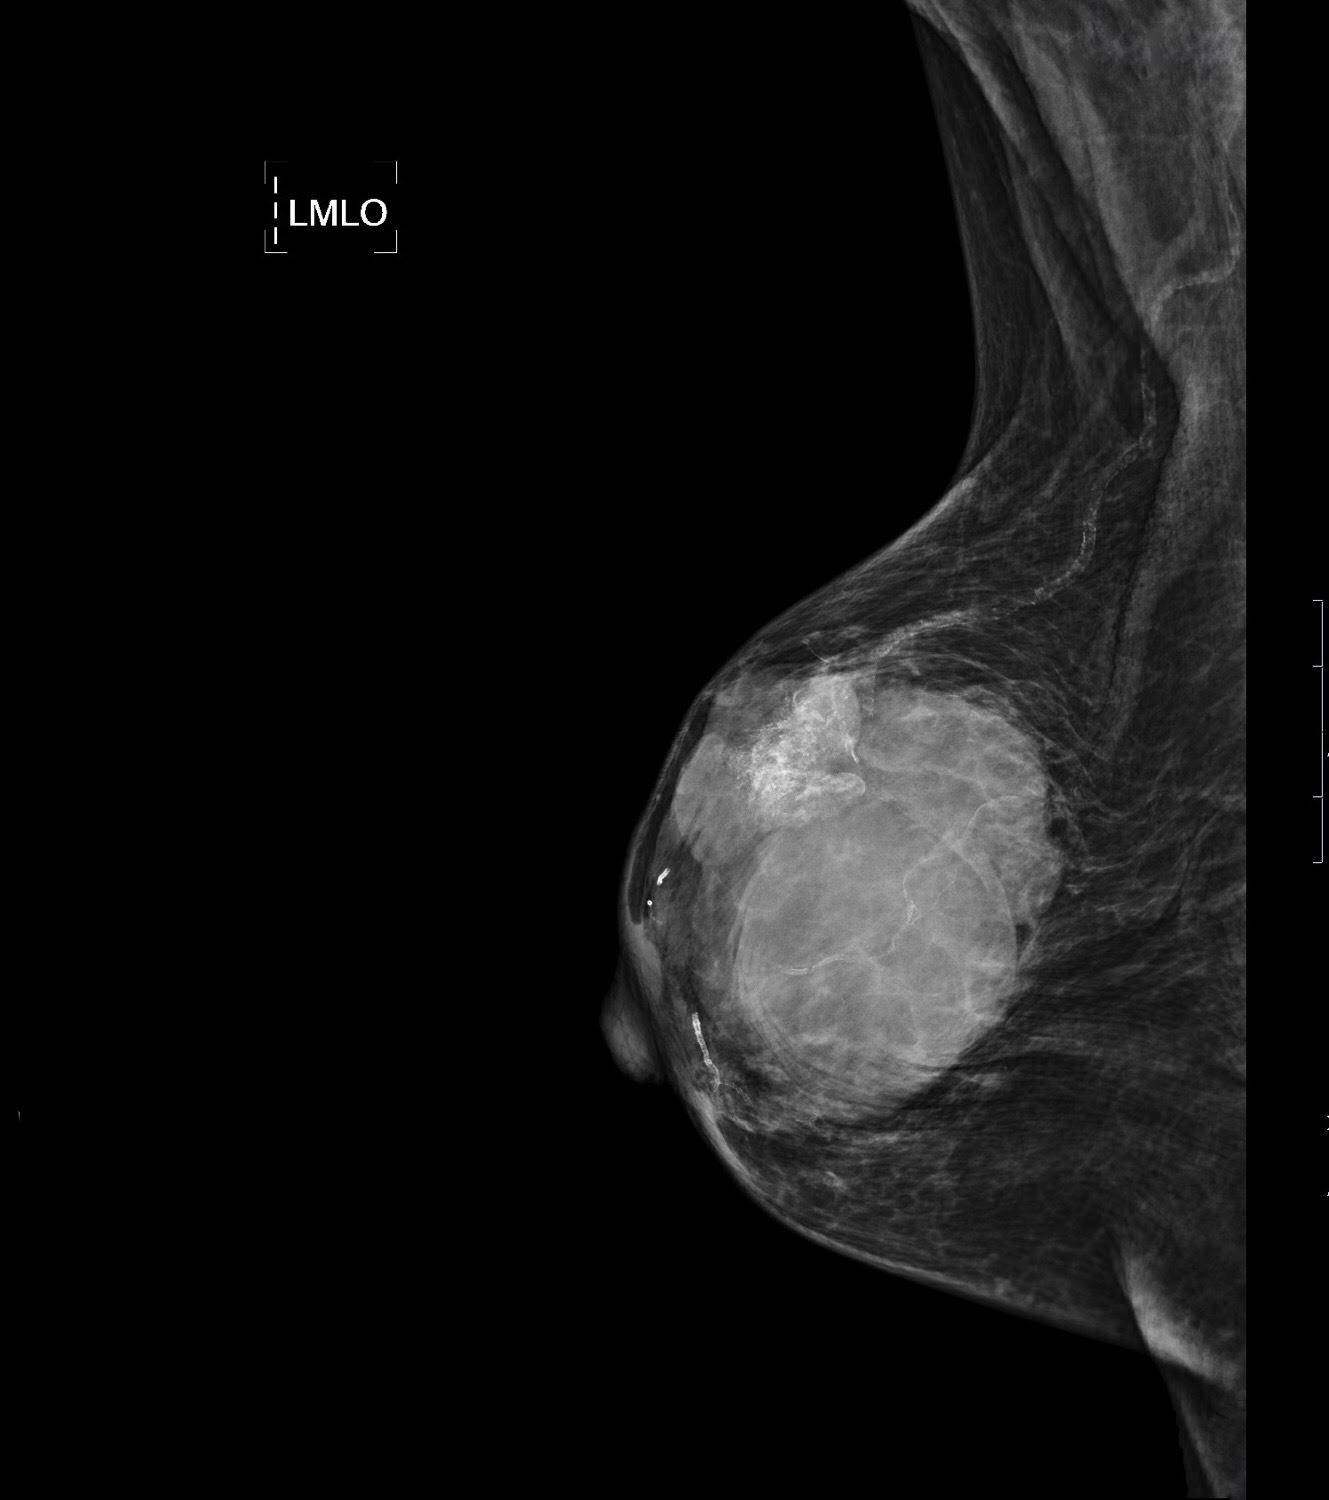

Caso 32

Aunque el rendimiento diagnóstico de la ecografía es superior al de la mamografía en los casos de parénquimas mamarios densos, mujeres menores de 35 años, este no es nuestro caso ya que se trata de una mujer de 85 años. La mamografía es la prueba de elección en mujeres mayores de 40 años pues se trata de una prueba de alta sensibilidad y especificidad para la detección del cáncer de mama. Además es de bajo coste, tiene gran disponibilidad, no es invasiva y no causa daño. Se realizará una proyección craneocaudal y mediolateral oblicua